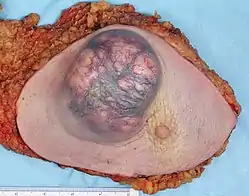

Liver cancer

Alcohol is a risk factor for liver cancer, through cirrhosis.[69][70][71] "Cirrhosis results from scar formation within the liver, most commonly due to chronic alcohol use."[72]

"Approximately 5 percent of people with cirrhosis develop liver cancer. Cirrhosis is a disease that develops when liver cells are replaced with scar tissue after damage from alcohol abuse, …"[73]

The NIAAA reports that "Prolonged, heavy drinking has been associated in many cases with primary liver cancer." However, it is liver cirrhosis, whether caused by alcohol or another factor, that is thought to induce the cancer."[74][75]

"The chances of getting liver cancer increase markedly with five or more drinks per day" (NCI).

A study concluded that for every additional drink regularly consumed per day, the incidence of liver cancer increases by 0.7 per 1000.[40]

In the United States, liver cancer is relatively uncommon, affecting approximately 2 people per 100,000, but excessive alcohol consumption is linked to as many as 36% of these cases by some investigators.[25][76] "Overall, 61% of HCC were attributable to HCV [hepatitis C virus], 13% to HBV [hepatitis B virus], and 18% to heavy alcohol drinking."[77] A study in the province of Brescia, northern Italy concluded, "On the basis of population attributable risks (AR), heavy alcohol intake seems to be the single most relevant cause of HCC in this area (AR: 45%), followed by HCV (AR: 36%), and HBV (AR: 22%) infection."[78]